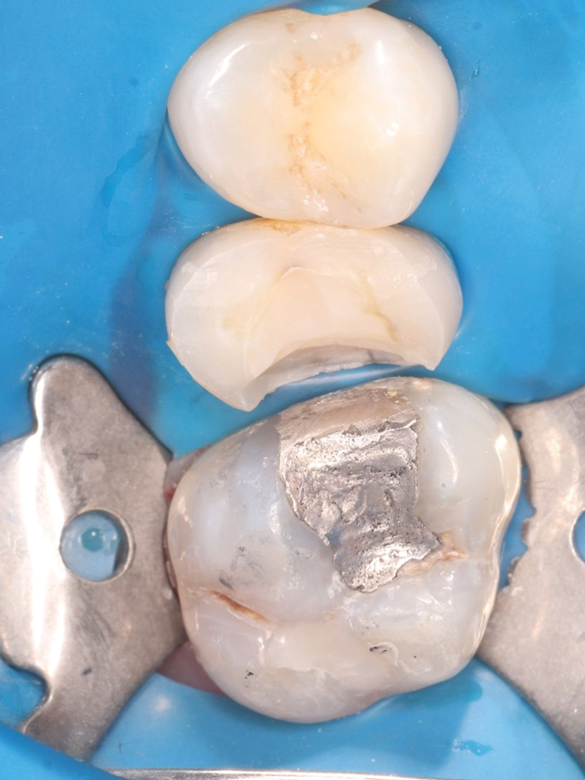

Fig 1 through Fig 5. Single-visit restoration of a maxillary second premolar following root canal treatment. Fig 1: Morphology-guided overlay preparation. Fig 2: IOS bite registration via imaging of buccal tooth surfaces. Fig 3: Preparation margin defined following IOS impression. Fig 4: Overlay design on the IOS platform, integrating adjacent tooth anatomy. Fig 5: Bonded overlay fabricated from CAD/CAM resin-based composite. Fig 6 through Fig 9. Digital workflow for guided endodontics using a digital twin, created by registering an IOI with CBCT data.

Figure 1

Figure 2

Figure 3

Figure 4

Figure 5

IOSs have found extensive applications across various dental specialties.1 In restorative dentistry, they are primarily used for fabricating dental restorations through CAD/CAM workflows, which remains by far their most widespread use (Figure 1 through Figure 5).2 The accuracy of IOSs enables dental professionals to produce restorations with precision that is on par with conventional methods.3 In addition to restorative dentistry, IOSs are being utilized for various applications in prosthodontics, orthodontics, forensic dentistry, and oral and maxillofacial surgery.